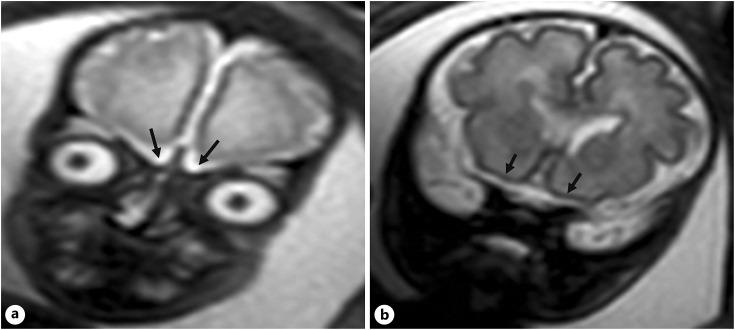

We prospectively evaluated OS development in fetuses diagnosed with CHDs from 2017 to 2021. Neurosonography was performed using transabdominal and transvaginal approaches after 30 weeks of gestation. OS assessment was conducted in the trans-frontal coronal plane, classifying their appearance as fully developed, hypoplastic, or absent. Abnormal OS cases underwent MRI and trio-based clinical exome sequencing (CES).

The study included 147 fetuses with CHD. Abnormal OS were found in 4 fetuses (2.7%) which also exhibited other additional anomalies. OS were absent in cases 1-3 and hypoplastic in case 4. MRI confirmed OS abnormalities in all cases, and trio-based CES identified a CHD7 gene mutation in cases 1, 2, and 4, supporting the diagnosis of CHARGE syndrome. Case 3 had normal trio-based CES results. No other CHARGE syndrome cases were diagnosed postnatally among the cases with normal OS.

该研究纳入了147例患有CHD的胎儿。4例胎儿(2.7%)发现OS异常,这些胎儿还表现出其他额外的异常。病例1 - 3的OS缺失,病例4的OS发育不全。MRI证实所有病例的OS均异常,基于三联体的CES在病例1、2和4中鉴定出CHD7基因突变,支持CHARGE综合征的诊断。病例3的基于三联体的CES结果正常。OS正常的病例中,出生后未诊断出其他CHARGE综合征病例。